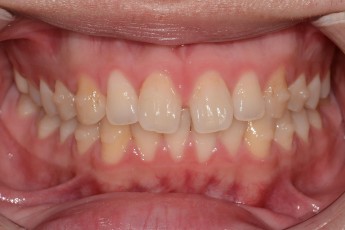

Before

After